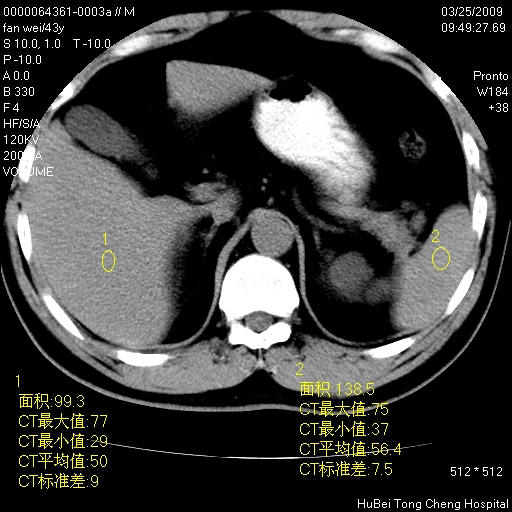

患者 男,43岁。左侧腰部不适两天。平素健康。无家族遗传病史。

腹部彩超提示:1)轻度脂肪肝。2)左肾多发囊性占位性病变;建议行进一步检查。

临床诊断:左肾多发囊性占位性病变,性质待定(多发肾囊肿?)。

双肾ct轴位平扫+增强扫描(层厚10mm,螺距1.0,重建间隔10mm),图像如下: